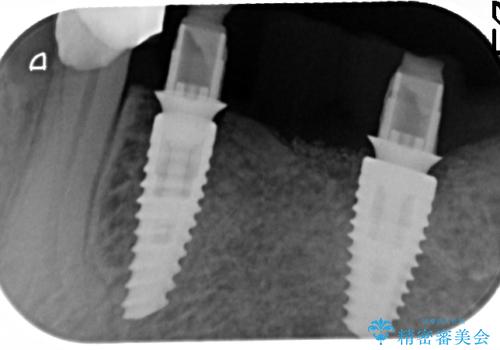

- 91万円(ストローマンインプラント×2・骨造成・チタンカスタムアバットメント×2・フルジルコニアクラウン×3)費用は治療当時の料金となります

インプラントを埋入することで入れ歯のように取り外しをする必要がなくしっかりと噛めるような状態になり、大変治療結果に満足していただくことができました。